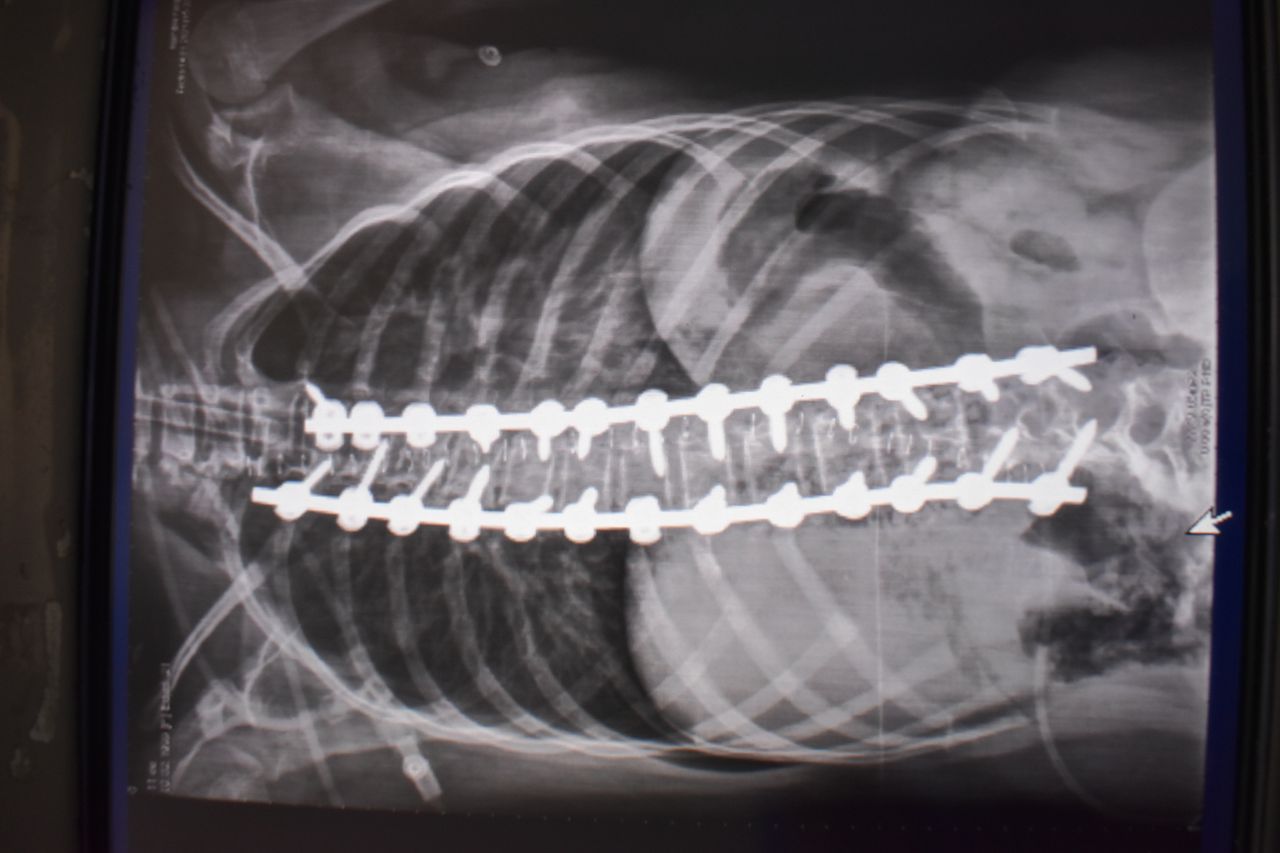

• Cirugía de columna

• Fusiones vertebrales amplias por vía anterior

• Fusiones vertebrales por vía posterior